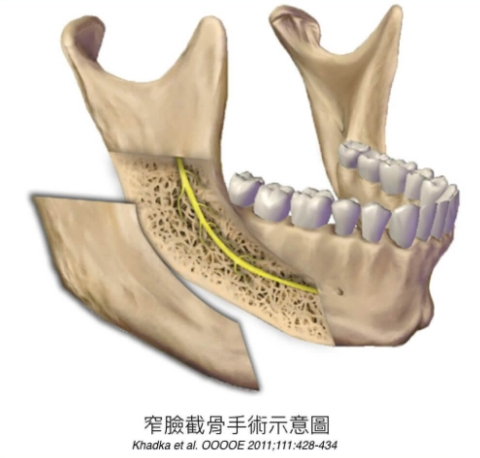

下顎削骨手術的傷口可以藏在耳後或是口腔內。因為口腔內傷口隱密性高,所以是現在較流行的手術方式。但口腔內傷口也有其缺點,其一是手術視野非常小,因此若醫師不熟悉解剖構造,則容易發生併發症,如:下顎骨折、下顎兩側不對稱或下顎凹陷等問題。其二是口腔內傷口會暫時導致口腔功能受損,但口腔內傷口癒合能力較身體其他組織來的快速,因此只會短暫的造成生活不便。

一般人較熟知的是V臉手術(V-Line osteotomy)、窄臉手術(splitting osteotomy)、下顎骨角切除(mandibular angle reduction)